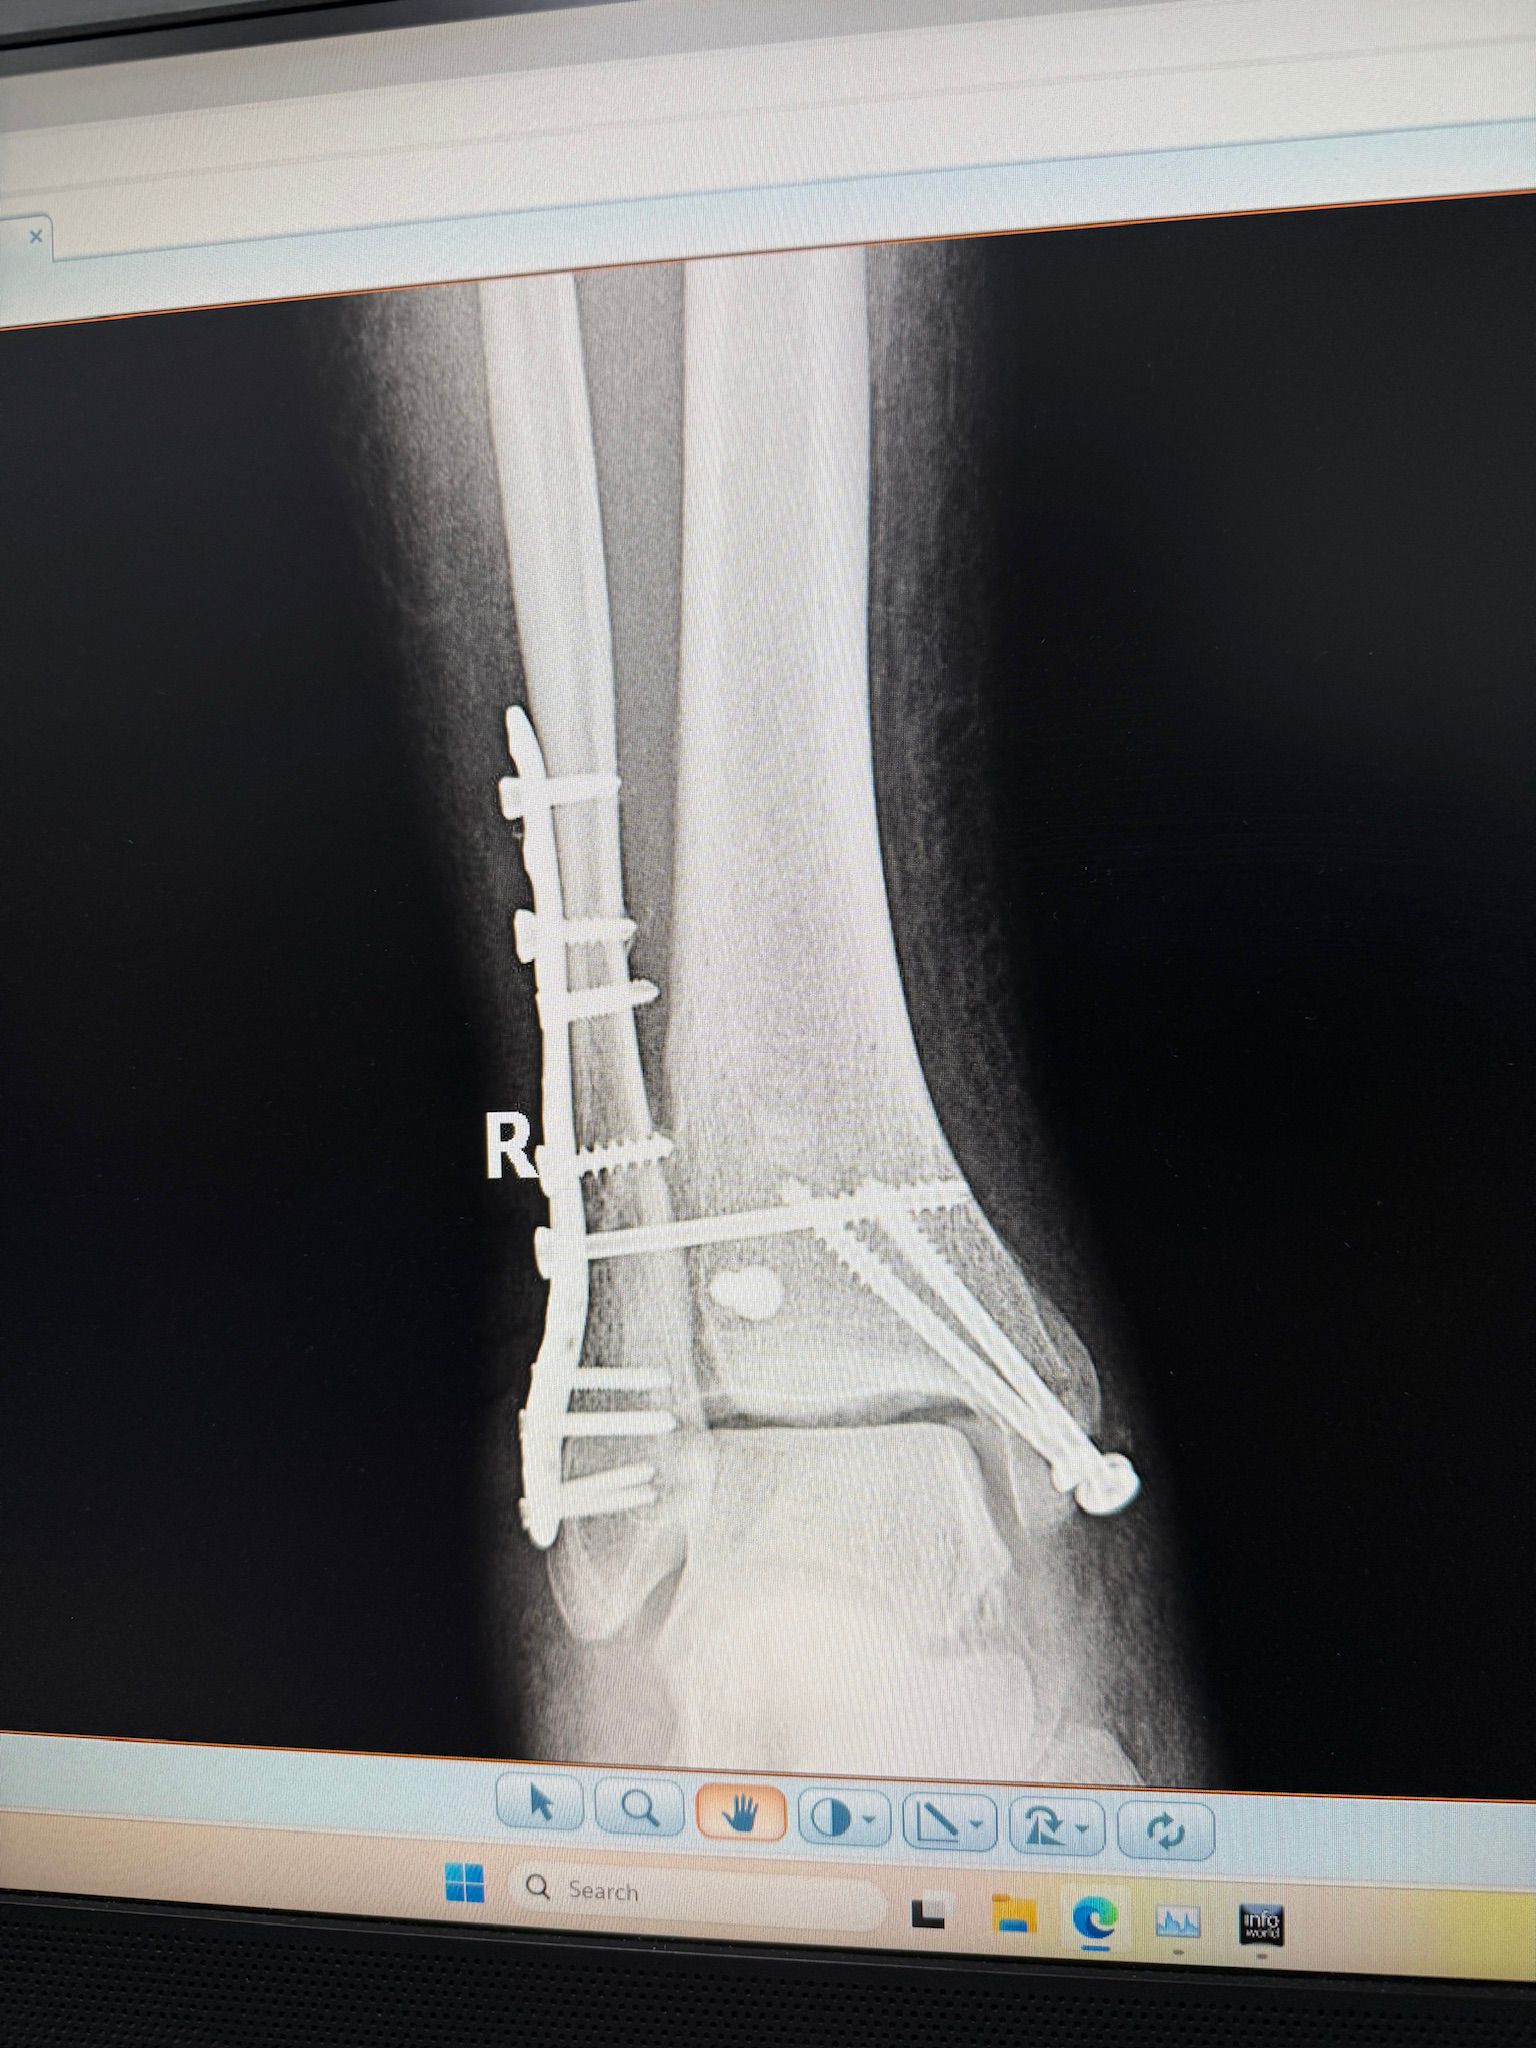

Imagini Clinice